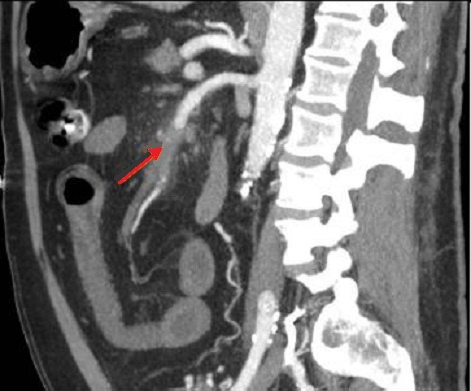

Image d'une thombus de artere

mesenterique superieure ( ischemie meresenterique

arterielle aigue ) en TDM phase arterielle ,coupe

sagitale . Sur cette coupe on peut

voyait ảrtere du tronc coeliaque en net et complete

, artere mesenterique superieure est en se voyait

encore d'une partie seul a hyper-dense . Image du

thrombus est iso-dense ( fleche jaune ) . Aspect de

pneumomatose de la paroi de l'intestin est encore se

voyait sur une portion verticale de l'intestin (

fleche rouge ) . Ischemie mesenterique arterielle

aigue en coupe TDM sagitale . |